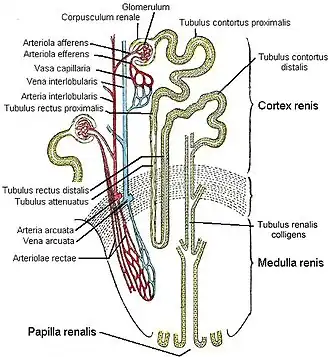

Jedes Glomerulum bildet zusammen mit seiner Bowmanschen Kapsel ein Nierenkörperchen (Corpusculum renale Malpighii). Und jedes Malpighische Nierenkörperchen bildet zusammen mit dem zugehörigen Nierenkanälchen (Tubulus) ein Nephron (von altgriechisch νεφρός nephros, deutsch ‚Niere‘) als kleinste funktionelle (morphologische, physiologische) Untereinheit der Niere von Menschen und anderen Wirbeltieren.[2]

Die funktionelle Grundeinheit der Niere ist das Nephron, das aus Nierenkörperchen und Nierenkanälchen besteht. Jede menschliche Niere verfügt über etwa eine Million Nephrone, und damit über ebenso viele Nierenkörperchen, Nierenknäuelchen und Nierenkanälchen.[3] Die Nierenkanälchen werden mitunter auch als Harnkanälchen beschrieben, weil in ihnen der Primärharn zum Sekundärharn (oder Endharn, Urin) konzentriert wird; analog werden die Nierenknäuelchen als Filterkörperchen erklärt.

Die prinzipielle Funktionsweise eines Nephrons lässt sich grob in zwei Prozesse unterteilen:

Im ersten Prozess, der im Nierenkörperchen stattfindet, wird aus dem Blut durch Querstromfiltration der Primärharn abgepresst. Bei dieser Filtration werden Bestandteile oberhalb einer bestimmten Größe, darunter die Blutkörperchen und größere Moleküle, zurückgehalten. Damit sind in dem Ultrafiltrat nur die niedermolekularen Bestandteile des Blutplasmas enthalten, darunter solche, die ausgeschieden werden sollen. Dieser Primärharn enthält aber auch – und überwiegend – zahlreiche Stoffe, die für den Körper wertvoll sind. Schon Galenos hat über die Nierenfiltration nachgedacht.[4] William Bowman bewies, dass Glomeruli und Tubuli eine funktionelle Einheit bilden.

In einem zweiten Prozess, der im Anschluss in den Nierenkanälchen abläuft, werden wertvolle Stoffe wie Zucker, Aminosäuren und Elektrolyte wieder kontrolliert in den Blutkreislauf zurückgeholt – resorbiert (Rückresorption). Weiterhin wird auch ein Großteil des abgefilterten Wassers resorbiert, das dem Körper nicht verloren gehen soll. Diese Vorgänge der Resorption laufen in verschiedenen Abschnitten des sich anschließenden, schlauchartigen Tubulussystems ab – und zusätzlich solche aktiver Sekretion von ausscheidungspflichtigen Substanzen in den Harn. Dieses Zusammenspiel von Rückresorption und Sekretion bezeichnet man als tubulären Transport; gewissermaßen entscheiden die Tubuli so über die Harnpflicht der einzelnen Elektrolyte. Die Nierenkanälchen konzentrieren den Primärharn somit zum Sekundärharn (Endharn), der sich im Nierenbecken (Pelvis renalis) sammelt – dem Beginn der Harnwege.

Feinbau

Der Feinbau der Niere zeichnet sich durch ein hochdifferenziertes Tubulussystem und eine spezifisch angepasste Blutversorgung aus. Das Tubulussystem lässt sich aufgrund der Embryonalentwicklung in zwei Teile gliedern, das Nephron und das Sammelrohr. Beide bilden eine funktionelle Einheit. Der letzte, das heißt sammelrohrnahe Nephronabschnitt ist embryologisch dem Sammelrohr zugeordnet.

Verzweigungen

Die Segmentarterien (siehe oben) teilen sich weiter auf. Eine Arteria interlobaris versorgt je zwei angrenzende Markpyramiden und entsprechende Rindenbereiche. Sie verläuft in den Rindensäulen entlang der Seiten der Pyramiden in Richtung Rinde, verzweigt sich aber an der Basis der Pyramide in Arteriae arcuatae. Diese verlaufen bogenförmig an der Mark-Rinden-Grenze und geben in rechtem Winkel die radiär nach oben durch die Rinde verlaufenden Arteriae corticales radiatae sowie ebenfalls nahezu rechtwinklig in Markrichtung die Arteriae rectae ab.

Erstes und zweites Kapillarbett

Aus diesen gehen schließlich die Vasa afferentia hervor, die sich zu je einem Kapillarknäuel, dem Glomerulus (siehe unten), aufteilen. Aus diesem ersten Kapillargebiet läuft das immer noch sauerstoffreiche Blut wieder im Vas efferens zusammen. Von dort tritt das Blut in ein zweites Kapillarbett ein, diesmal zur Versorgung des Nierengewebes. Dabei muss man zwei Fälle je nach Lage des Glomerulus unterscheiden: Aus oberflächlichen Glomeruli, die im oberen Bereich der Rinde zur Organkapsel hin liegen, gelangt das Blut in das peritubuläre Kapillarnetz der Rinde, das die dort gelegenen Tubuli umspinnt. Aus juxtamedullären Glomeruli jedoch, die tiefer zur Mark-Rinden-Grenze hin liegen, entspringen die Gefäße zur Versorgung des Marks.

Die Versorgung des Marks

Diese kapillären Gefäße zur Versorgung des Marks sind die Vasa recta, die ganz gerade oft bis zur Papillenspitze absteigen und wieder in umgekehrter Richtung aufsteigen. Es gibt zahlreiche Querverbindungen zwischen ab- und aufsteigendem Schenkel. Die besondere Gefäßarchitektur des Marks ist von großer funktioneller Bedeutung für die Fähigkeit der Niere zur Harnkonzentrierung. Mit Hilfe des Gegenstromprinzips erzeugt die Niere zur Papillenspitze hin einen erheblichen osmotischen Gradienten (siehe unten), der ausgewaschen würde, wäre das Mark mit einem normalen Kapillarnetz versorgt. Der Preis dafür ist aber eine sehr schlechte Sauerstoffversorgung des Nierenmarks, da der Sauerstoff aus dem sauerstoffreichen, absteigenden Schenkel der Vasa recta direkt schon oben in den aufsteigenden, sauerstoffarmen Schenkel diffundieren kann.

Nephron

Die Niere besteht aus zahlreichen Einheiten, den Nephronen, in denen der Harn gebildet wird. Jede der menschlichen Nieren enthält 1 bis 1,4 Mio. Nephrone. Das Nephron selbst besteht aus einem Nierenkörperchen (Corpusculum renis) und einem Tubulusapparat.

Im Nierenkörperchen befindet sich der Glomerulus (auch das Glomerulum genannt), ein Gefäßknäuel, durch dessen gefensterte Kapillarwände der Primärharn abfiltriert wird. Der Primärharn tritt am Harnpol (siehe Abbildung) aus dem Nierenkörperchen in den proximalen Tubulus und in die Henlesche Schleife über, wo er nach dem Gegenstromprinzip aufkonzentriert wird. Es folgen der distale Tubulus und ein Sammelrohr (Tubulus renalis colligens).